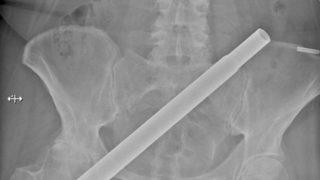

Her şey bir anda oldu! Ayağı kayıp düşen kadının kalçasına metal direk saplandı

15-08-2022 17:06

Kuzey İrlanda’nın Newry bölgesinde yaşayan 54 yaşındaki ismi açıklanmayan bir kadının başına gelen ilginç bir olay klinik vakaların incelendiği bir tıp dergisine konu oldu. İsmi açıklanmayan kadın olayın sonrasında hayatta kalabildiği için şanslı olduğunu ve kazaya hâlâ inanamadığını söyledi.